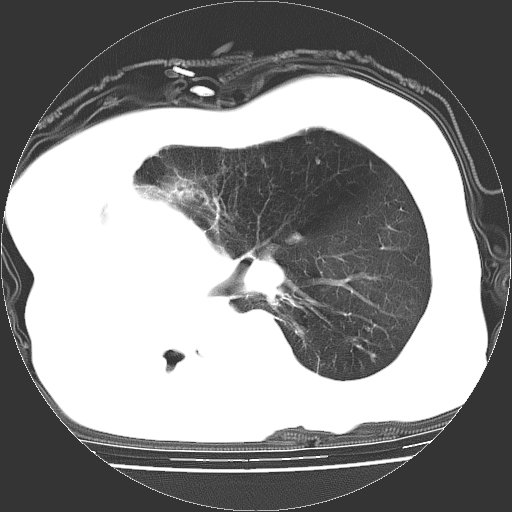

女,72岁,咳嗽、憋气一周,十年前曾患肺结核及胸膜结核。

右侧毁损肺,右侧纵隔疝

右侧毁损肺,右侧纵隔疝,左肺代偿!

右侧肺硬变,左肺代偿气肿。

1.右侧损毁肺伴胸膜钙化,2.左肺小结节灶,良性可能大,注意复查。3.肝脏左叶囊肿。4.先天性一侧肺不发育待出外(右侧胸廓无明显塌陷)。对比原片应该非常有帮助。

右侧肺毁损,左肺代偿性肺气肿,纵隔疝。